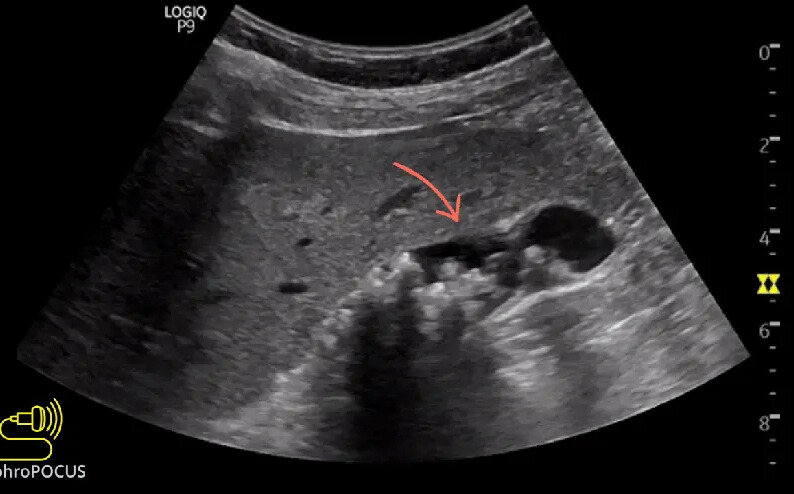

• Ultrasound → First-line, often shows fatty changes